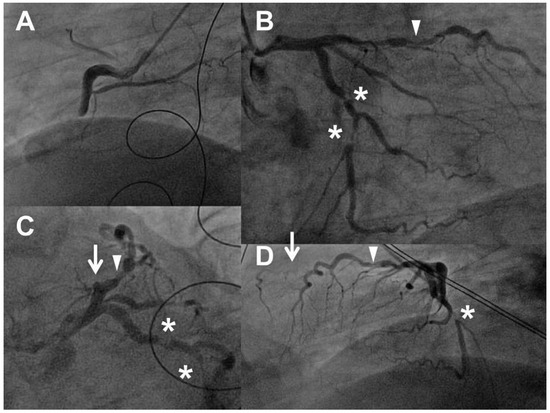

Radiofrequency Ablation of Atrial Tachycardia from ''No-Man's Land"

by Nikola Pavlović, Sven Knecht, Aline Mühl, Tobias Reichlin, Beat Schaer, Stefan Osswald, Christian Sticherling and Michael Kühne

Cardiovasc. Med. 2015, 18(3), 103; https://doi.org/10.4414/cvm.2015.00322 (registering DOI) - 18 Mar 2015

Atrial tachycardias can originate from almost any part of the atria, with a predilection for certain anatomical structures. Tachycardias originating from the peri-atrioventricular nodal region are rare, and can be challenging to ablate owing to the potential risk of atrioventricular block. We describe [...] Read more.

Atrial tachycardias can originate from almost any part of the atria, with a predilection for certain anatomical structures. Tachycardias originating from the peri-atrioventricular nodal region are rare, and can be challenging to ablate owing to the potential risk of atrioventricular block. We describe a patient with peri-nodal atrial tachycardia that was successfully ablated from the non-coronary aortic cusp. Full article